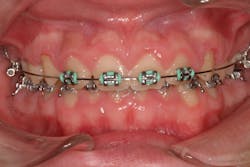

- Antihypertensives (calcium channel blockers such as nifedipine, amlodipine, and verapamil)

- 10% to 20% of the cases are typically attributed to calcium channel blockers, with nifedipine being the most notable problem (figures 4a and 4b).